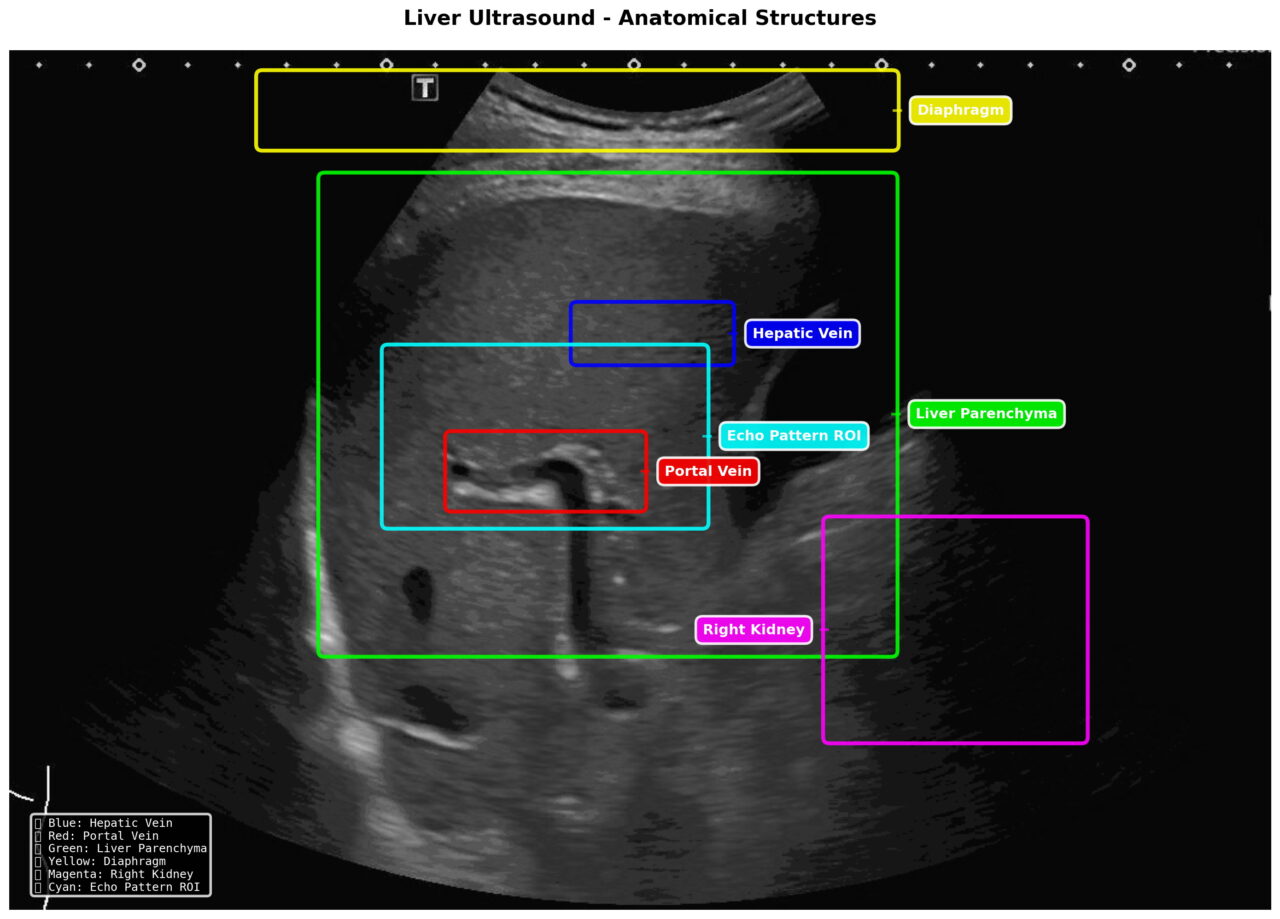

“นาโน” บอกว่า SmartLiva ทำงานเหมือนอัปเกรดจากภาพอัลตราซาวด์ขาวดำธรรมดาให้กลายเป็นผลวินิจฉัยที่อ่านง่ายและแม่นยำ โดยแพทย์อัปโหลดภาพผ่านเว็บได้ทั้งบนคอมพิวเตอร์หรือแท็บเล็ต จากนั้นระบบจะช่วยปรับภาพให้ชัดขึ้น คัดเฉพาะบริเวณเนื้อตับที่ต้องวิเคราะห์ และทำให้ภาพดูเข้าใจง่ายขึ้นด้วยการไฮไลต์เป็นสี เช่น ตับเป็นสีแดง ไขมันเป็นสีเหลือง เพื่อให้เห็นความผิดปกติได้ทันที โดย AI จะทำการประเมิน 3 เรื่องพร้อมกัน คือ ประเมินระดับพังผืด/ความแข็งของตับ (F0–F4), ตรวจหาความผิดปกติของเนื้อเยื่ออย่างถุงน้ำหรือมะเร็งตับ และตรวจหาพยาธิใบไม้ตับ ซึ่งตัว AI จะทำการประมวล วิเคราะห์ และสรุปผลออกมาเป็นรายงานพร้อมภาพประกอบและคำอธิบายที่คนทั่วไปเข้าใจได้ โดย AI ทั้งหมดถูกฝึกฝน (Train) ด้วยฐานข้อมูลภาพอัลตราซาวด์กว่า 50,000 ภาพ จากโรงพยาบาลชั้นนำ อย่างโรงพยาบาลขอนแก่น โรงพยาบาลจุฬาลงกรณ์ และโรงพยาบาลรามาธิบดี